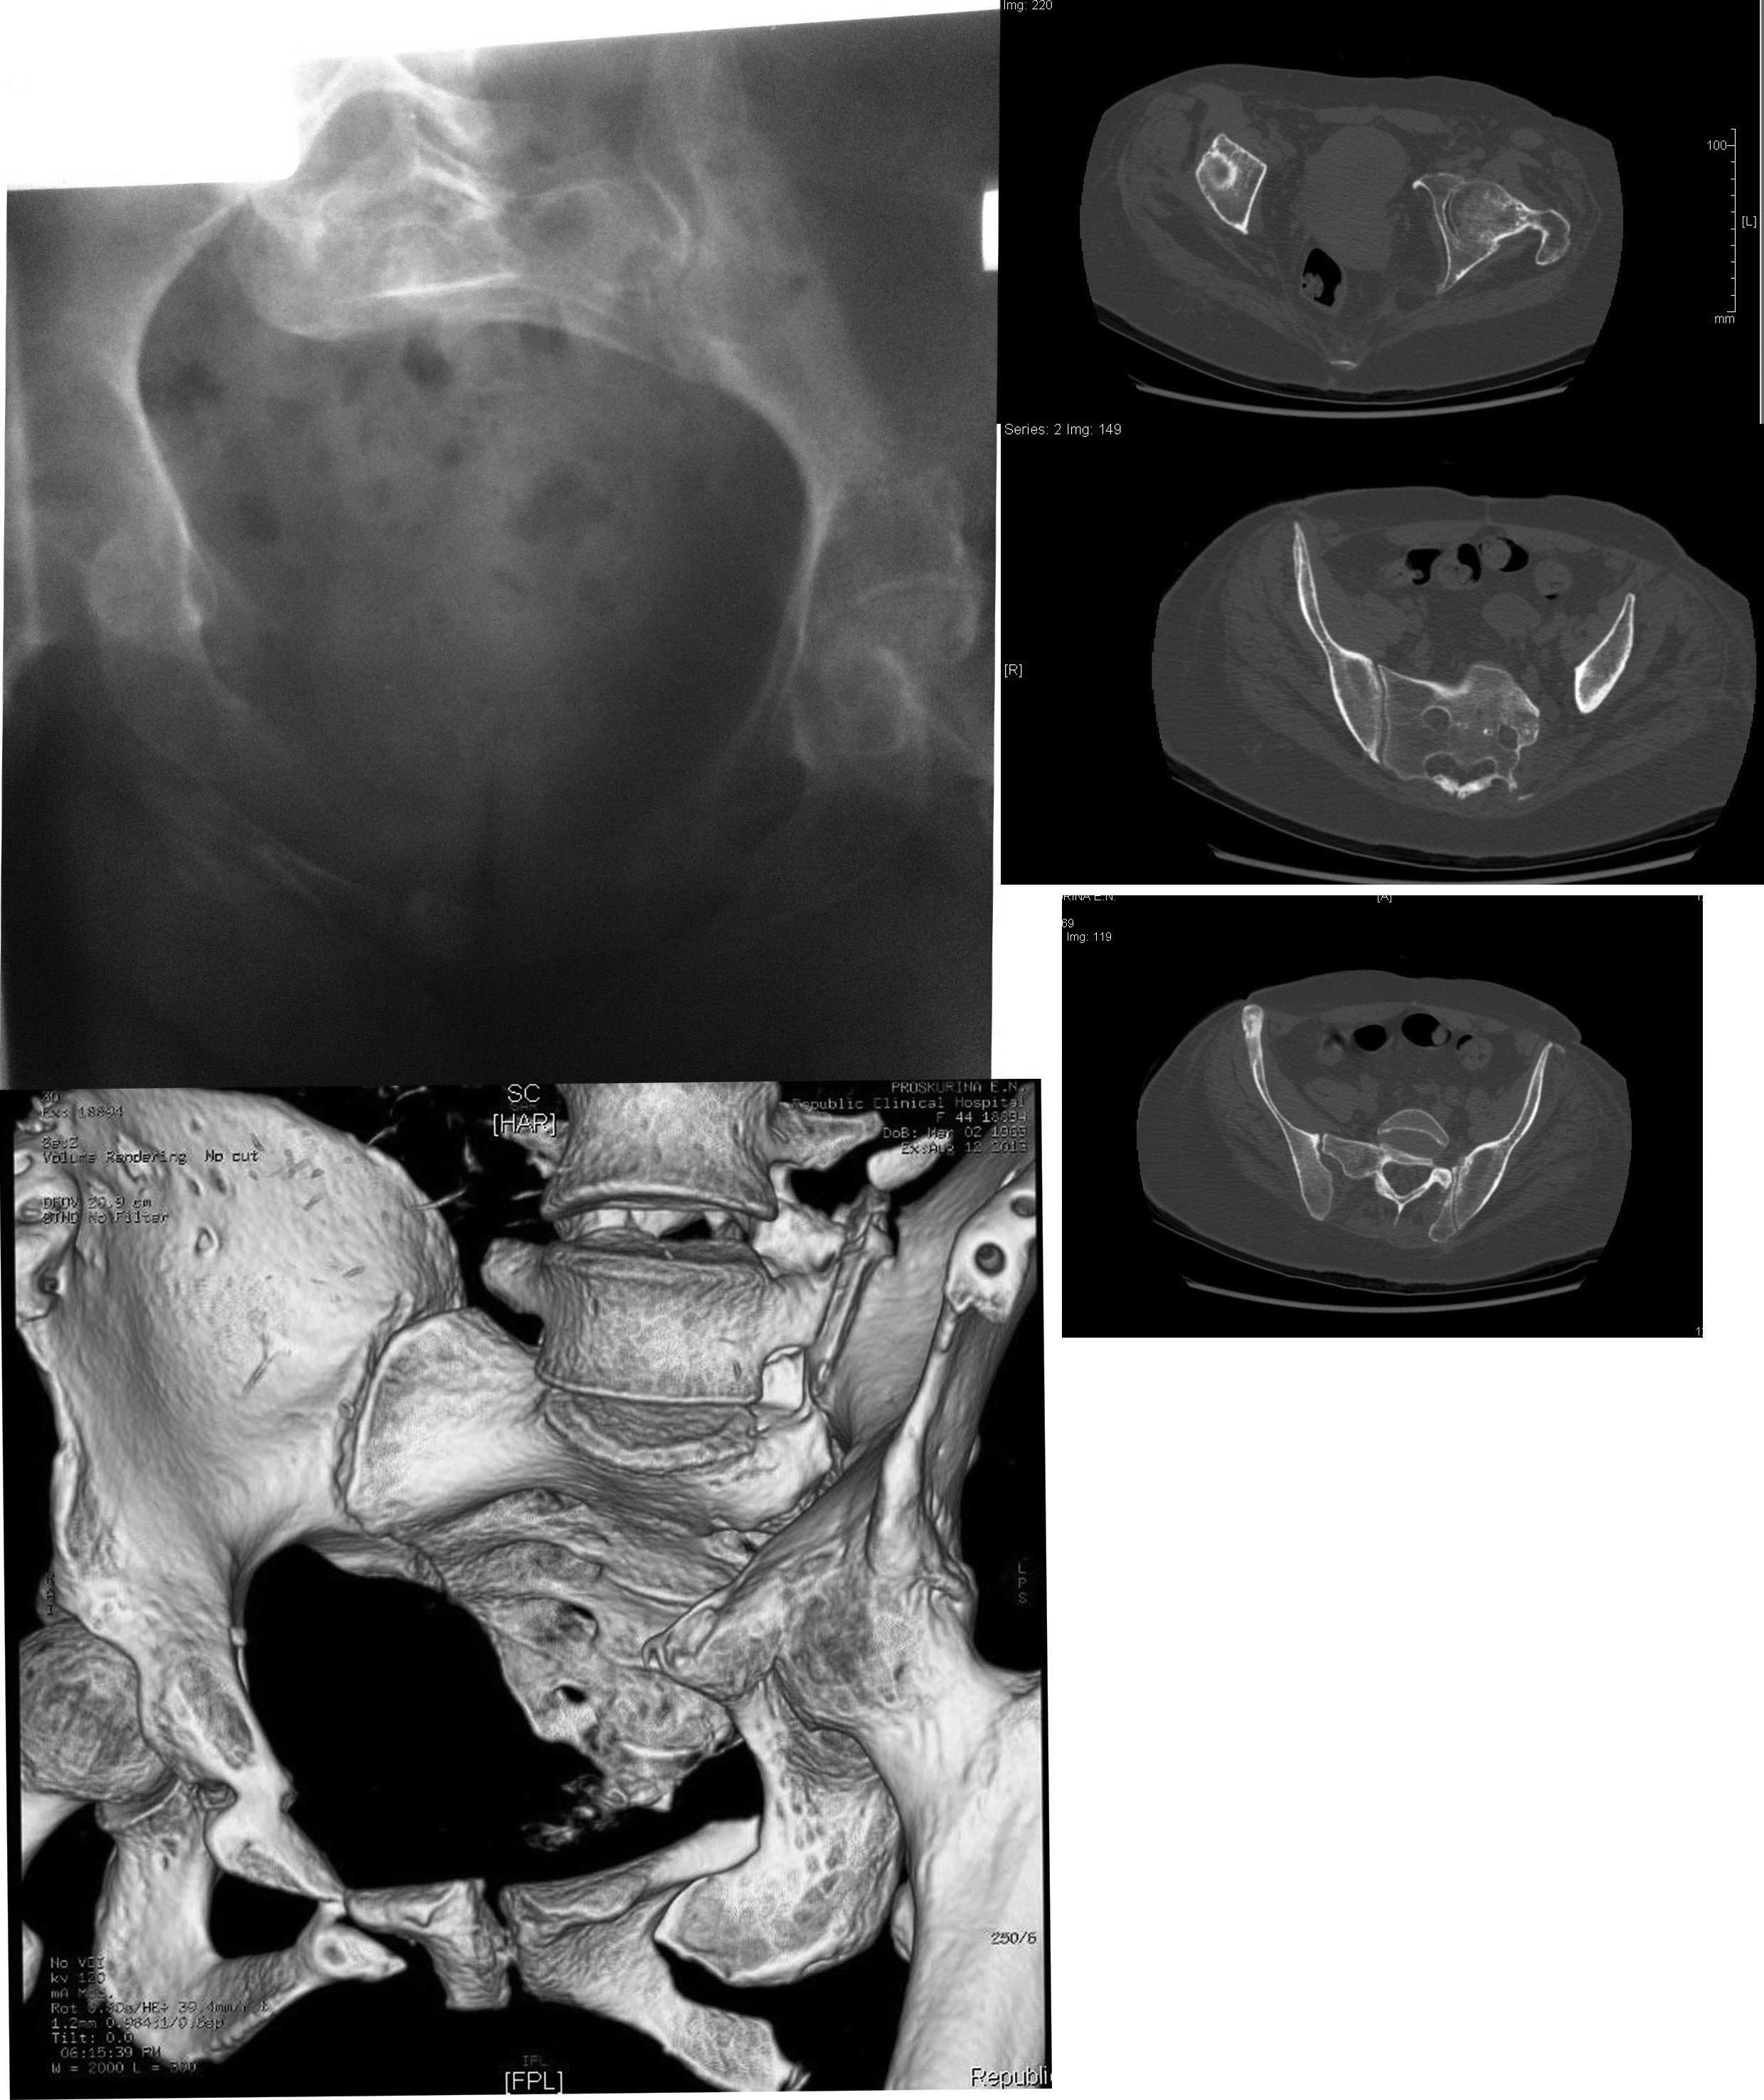

Пациентка П. 44г., травма в 2011г автодорожная. Первично - доставлена в

областную клинику, где после соответствующего противошокового лечения

(лапоротомия по по поводу разрыва мочевого пузыря) применен АВФ, который

"носила" 6 месяцев. После демонтажа перелом не сросся. В 2012г по квоте

в Кургане вновь о/синтез АВФ. Прошло 11 месяцев, неделю назад аппарат

демонтирован. На сегодня передвигается только с помощью костылей,

беспокоят боли в левом крестцово-подвздошном сочленении. Клинически:

левая нога укорочена на 5см, подвижность в левом т/бедренном суставе

отсутствует, тугая подвижность в левом крестцово-подвздошном сочленении.

На Rx таза нет сращения переднего полукольца и тугой л/сустав крестца

слева, анкилоз левого т/бедренного сустава. Учитывая молодой возраст

думаю, что пациентку можно поставить на ноги. Что делать?